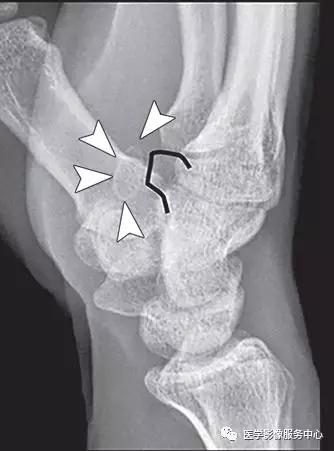

背侧三角骨骨折:

(左)在三角骨水平的背侧腕关节软组织内可见小撕脱骨片影。(右)腕骨间背侧韧带(白色箭头)从其在背侧三角骨(Tq)连接处(黑色箭头)的撕脱骨折(黑色长剪头)。